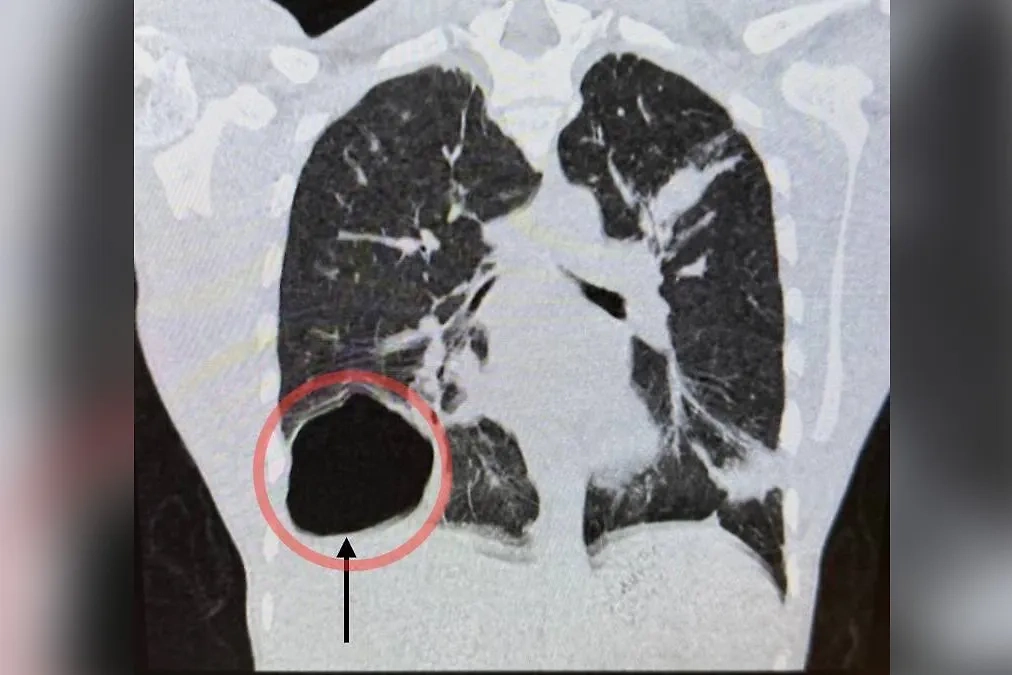

Снимок лёгкого с гигантской паразитарной кистой. Фото © VK / ГБУЗ МО «МОЦОМД»

17-летний подросток поступил в Московский областной центр охраны материнства и детства с жалобами на слабость, высокую температуру, кашель и боль в правой половине грудной клетки. Врачи провели диагностику и обнаружили паразитарную кисту правого лёгкого, размер которой был сопоставим с головой новорождённого ребёнка.